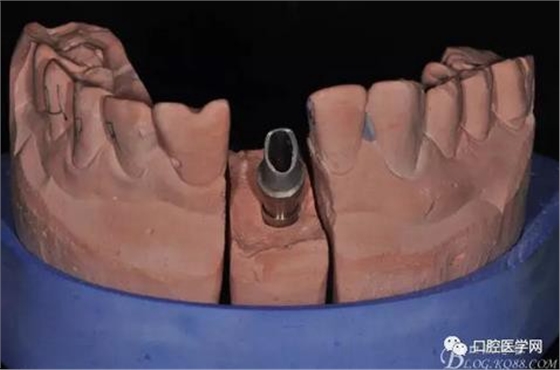

圖16 修復基臺模型頜面照